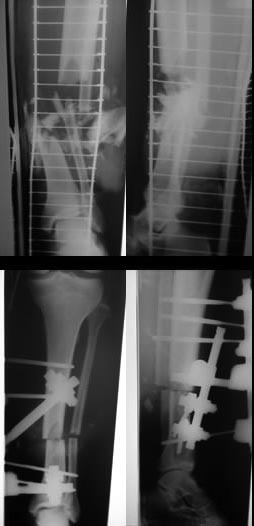

[Ortho] Тяжелая производственная травма: открытый перелом голени (тип IIIВ по Gustillo-Andersen)